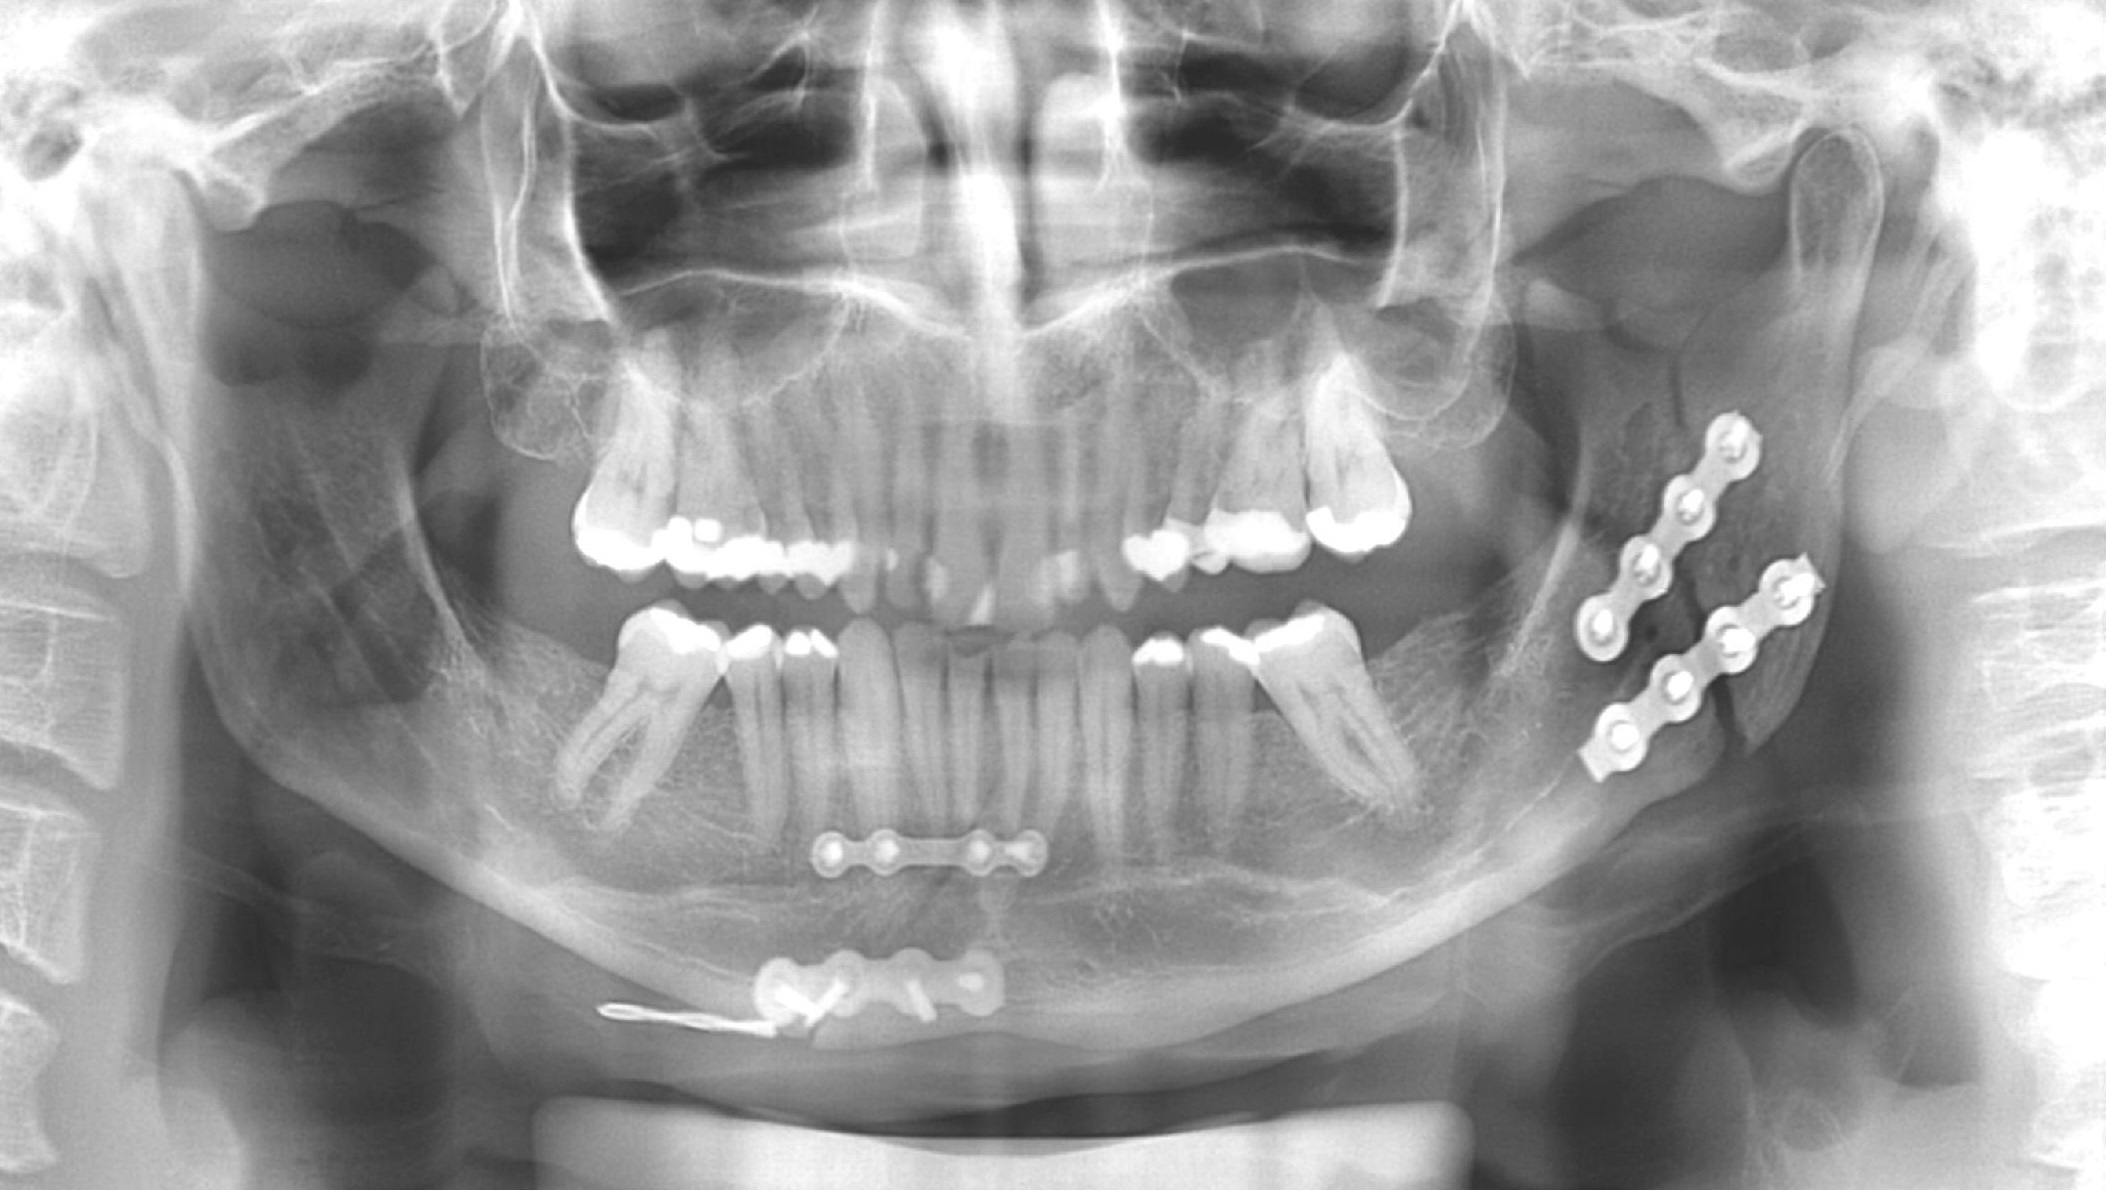

Nesses casos, o cirurgião buco-maxilo-facial é o profissional mais adequado para o tratamento das fraturas, ferimentos orais e faciais e tudo que está envolvido em todos os aspectos do tratamento.

Fraturas nos ossos da face também podem ocasionar desoclusão, que é a mordida errada dos dentes. Se não foram tratadas, podem ocasionar uma série de outros problemas funcionais.